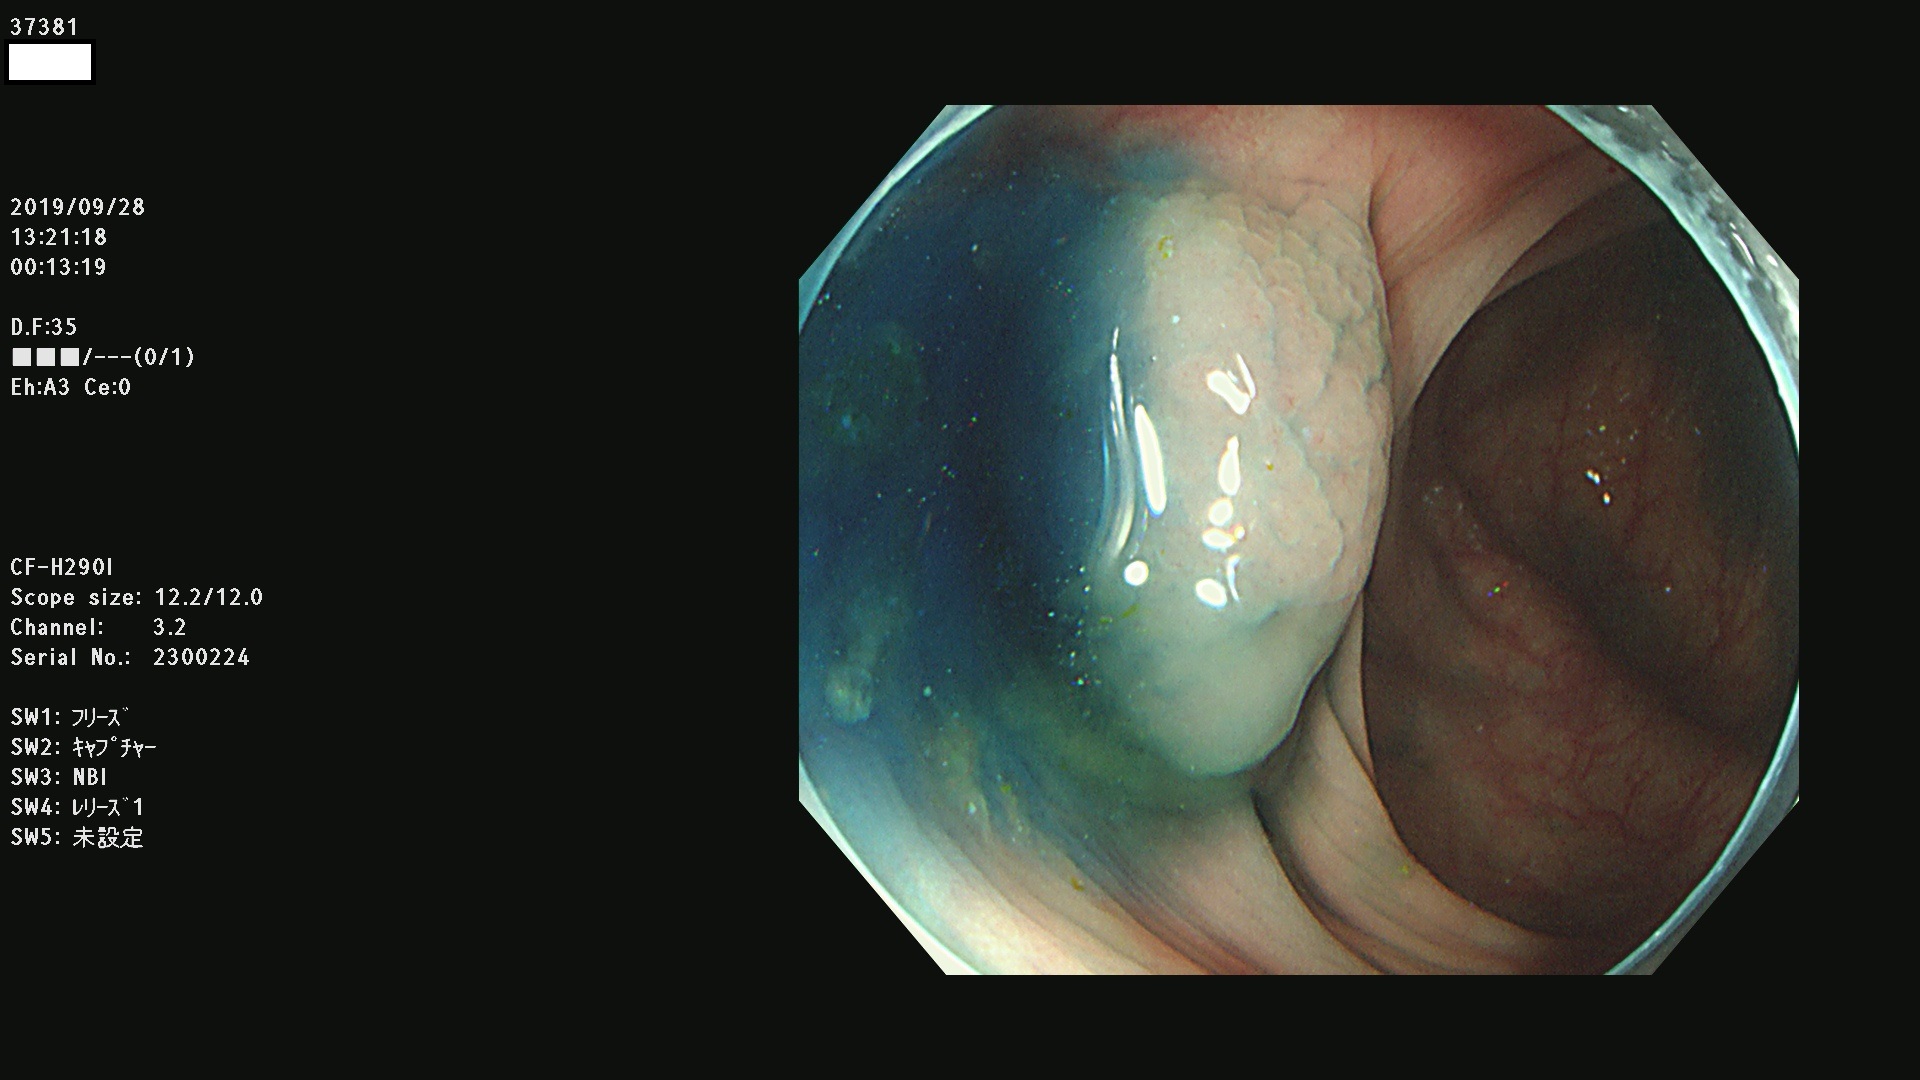

37300(SSAPのみ) 37301 37303 37304 37306 37307 37308 37309 37312 37313 37315(SSAPのみ) 37316 37317(SSAPのみ) 37319 37321(SSAPのみ) 37322 37323 37324 37325 37326 37328(SSAPのみ) 37329 37330 37331 37332(SSAPのみ) 37333 37334 37336 37337 37338 37340 37342 37343(SSAPのみ) 37344 37345 37346 37347 37348 37352(SSAPのみ) 37353 37354 37355 37356 37358 37360 37361(SSAPのみ) 37362 37363 37366 37367 37369 37370 37371 37372(SSAPのみ) 37375 37376 37377 37380 37381(SSAPのみ) 37382 37383 37384 37385(SSAPのみ) 37386 37387 37388 37389 37390 37392(SSAPのみ) 37393 37394 37395 37396(SSAPのみ) 37397 37398(SSAPのみ) 37399

発見困難で危険性の高い平坦型病変(上記100名より抽出) )